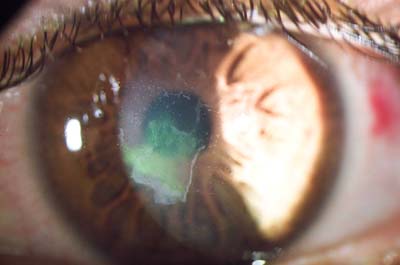

Cicatriz por Trauma

Cicatriz por Trauma